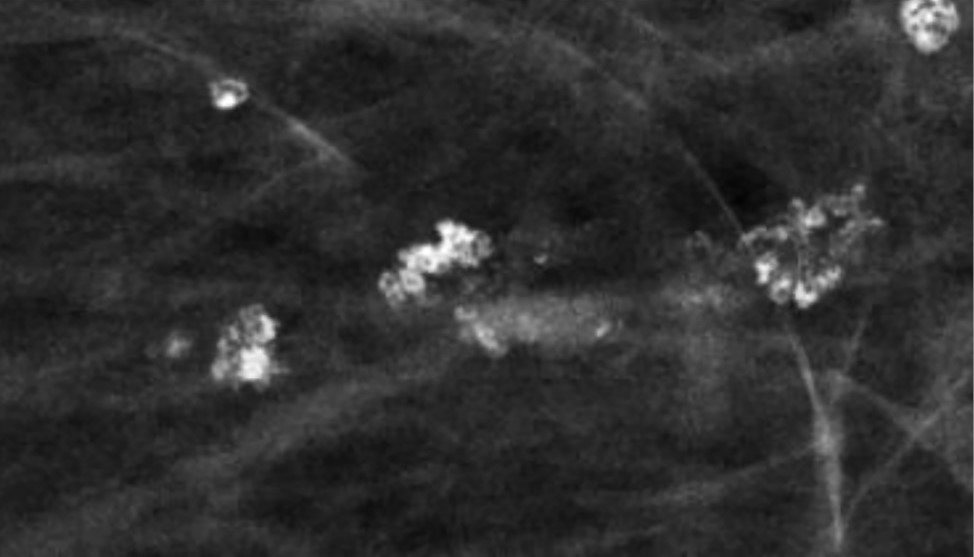

Микрокальцинатами принято называть депозиты кальция в ткани молочной железы размером менее 0,5 мм. В подавляющем большинстве случаев в молочных железах определяются микрокальцинаты именно доброкачественного генеза. Отмечается, что они встречаются примерно у половины обследуемых женщин.

Считается, что микрокальцификация возникает из-за отложения солей, которое является результатом различных физиологических процессов: секреторного, воспалительного, инволютивного, травматизации, некроза [12].

Множественные рассеянные точечные микрокальцинаты характерны для склерозирующего аденоза – доброкачественного состояния, при котором отмечается увеличение долек молочных желез и их дисторция окружающей фиброзной тканью [13] (Рис.7).